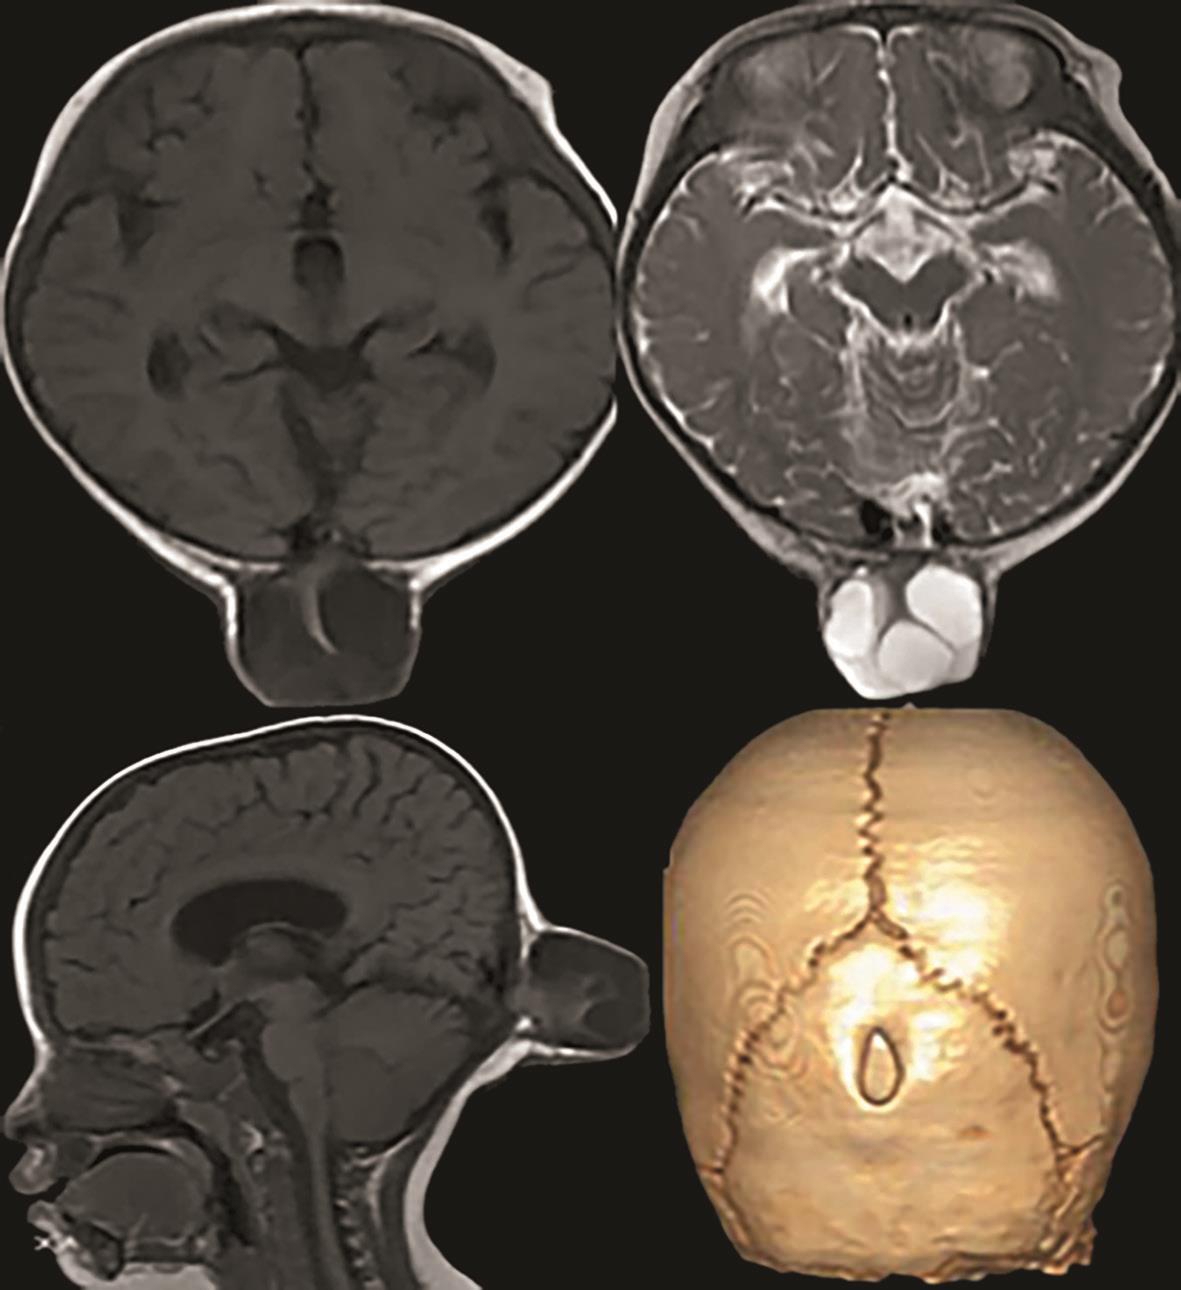

3.辅助检查 头颅CT示枕骨局部缺损,枕部脑膜膨出。头颅MRI示枕部脑膜膨出(图4-1-1)。

图4-1-1 头颅MRI示枕部脑膜膨出

辅助检查:颈椎MRI提示Chiari畸形,合并颈髓空洞(图4-1-2)。

初步诊断:Chiari畸形Ⅰ型。

图4-1-2 颈椎MRI

(5)辅助检查:MRI可见小脑扁桃体下疝,合并颈髓空洞。

①颅后窝极度增大,伴横窦及窦汇抬高,超过人字缝;②天幕上抬超过人字缝,在冠状位和矢状位上显示尤清;③巨大的囊肿占据了颅后窝中线的绝大部分,并与扩大的第四脑室相通;④常伴有不同程度的脑积水,导水管扭结不通,小脑下蚓部缺如;⑤上蚓部被扩大的第四脑室及后方的囊腔推挤向前上方移位(图4-1-3)。需借助MRI与Blake囊肿、巨脑池、蛛网膜囊肿、单纯蚓部及小脑发育不全鉴别。

图4-1-3 患儿上蚓部向前上方移位

辅助检查:头颅MRI(图4-1-4)检查示双侧脑室系统对称性显著扩大,脑室前、后角变钝,双侧大脑半球脑实质明显变薄,脑实质内未见明确异常信号,颅后窝枕大池扩大,双侧小脑半球受压、上抬,小脑幕抬高,小脑蚓部缺如。

图4-1-4 头颅MRI检查